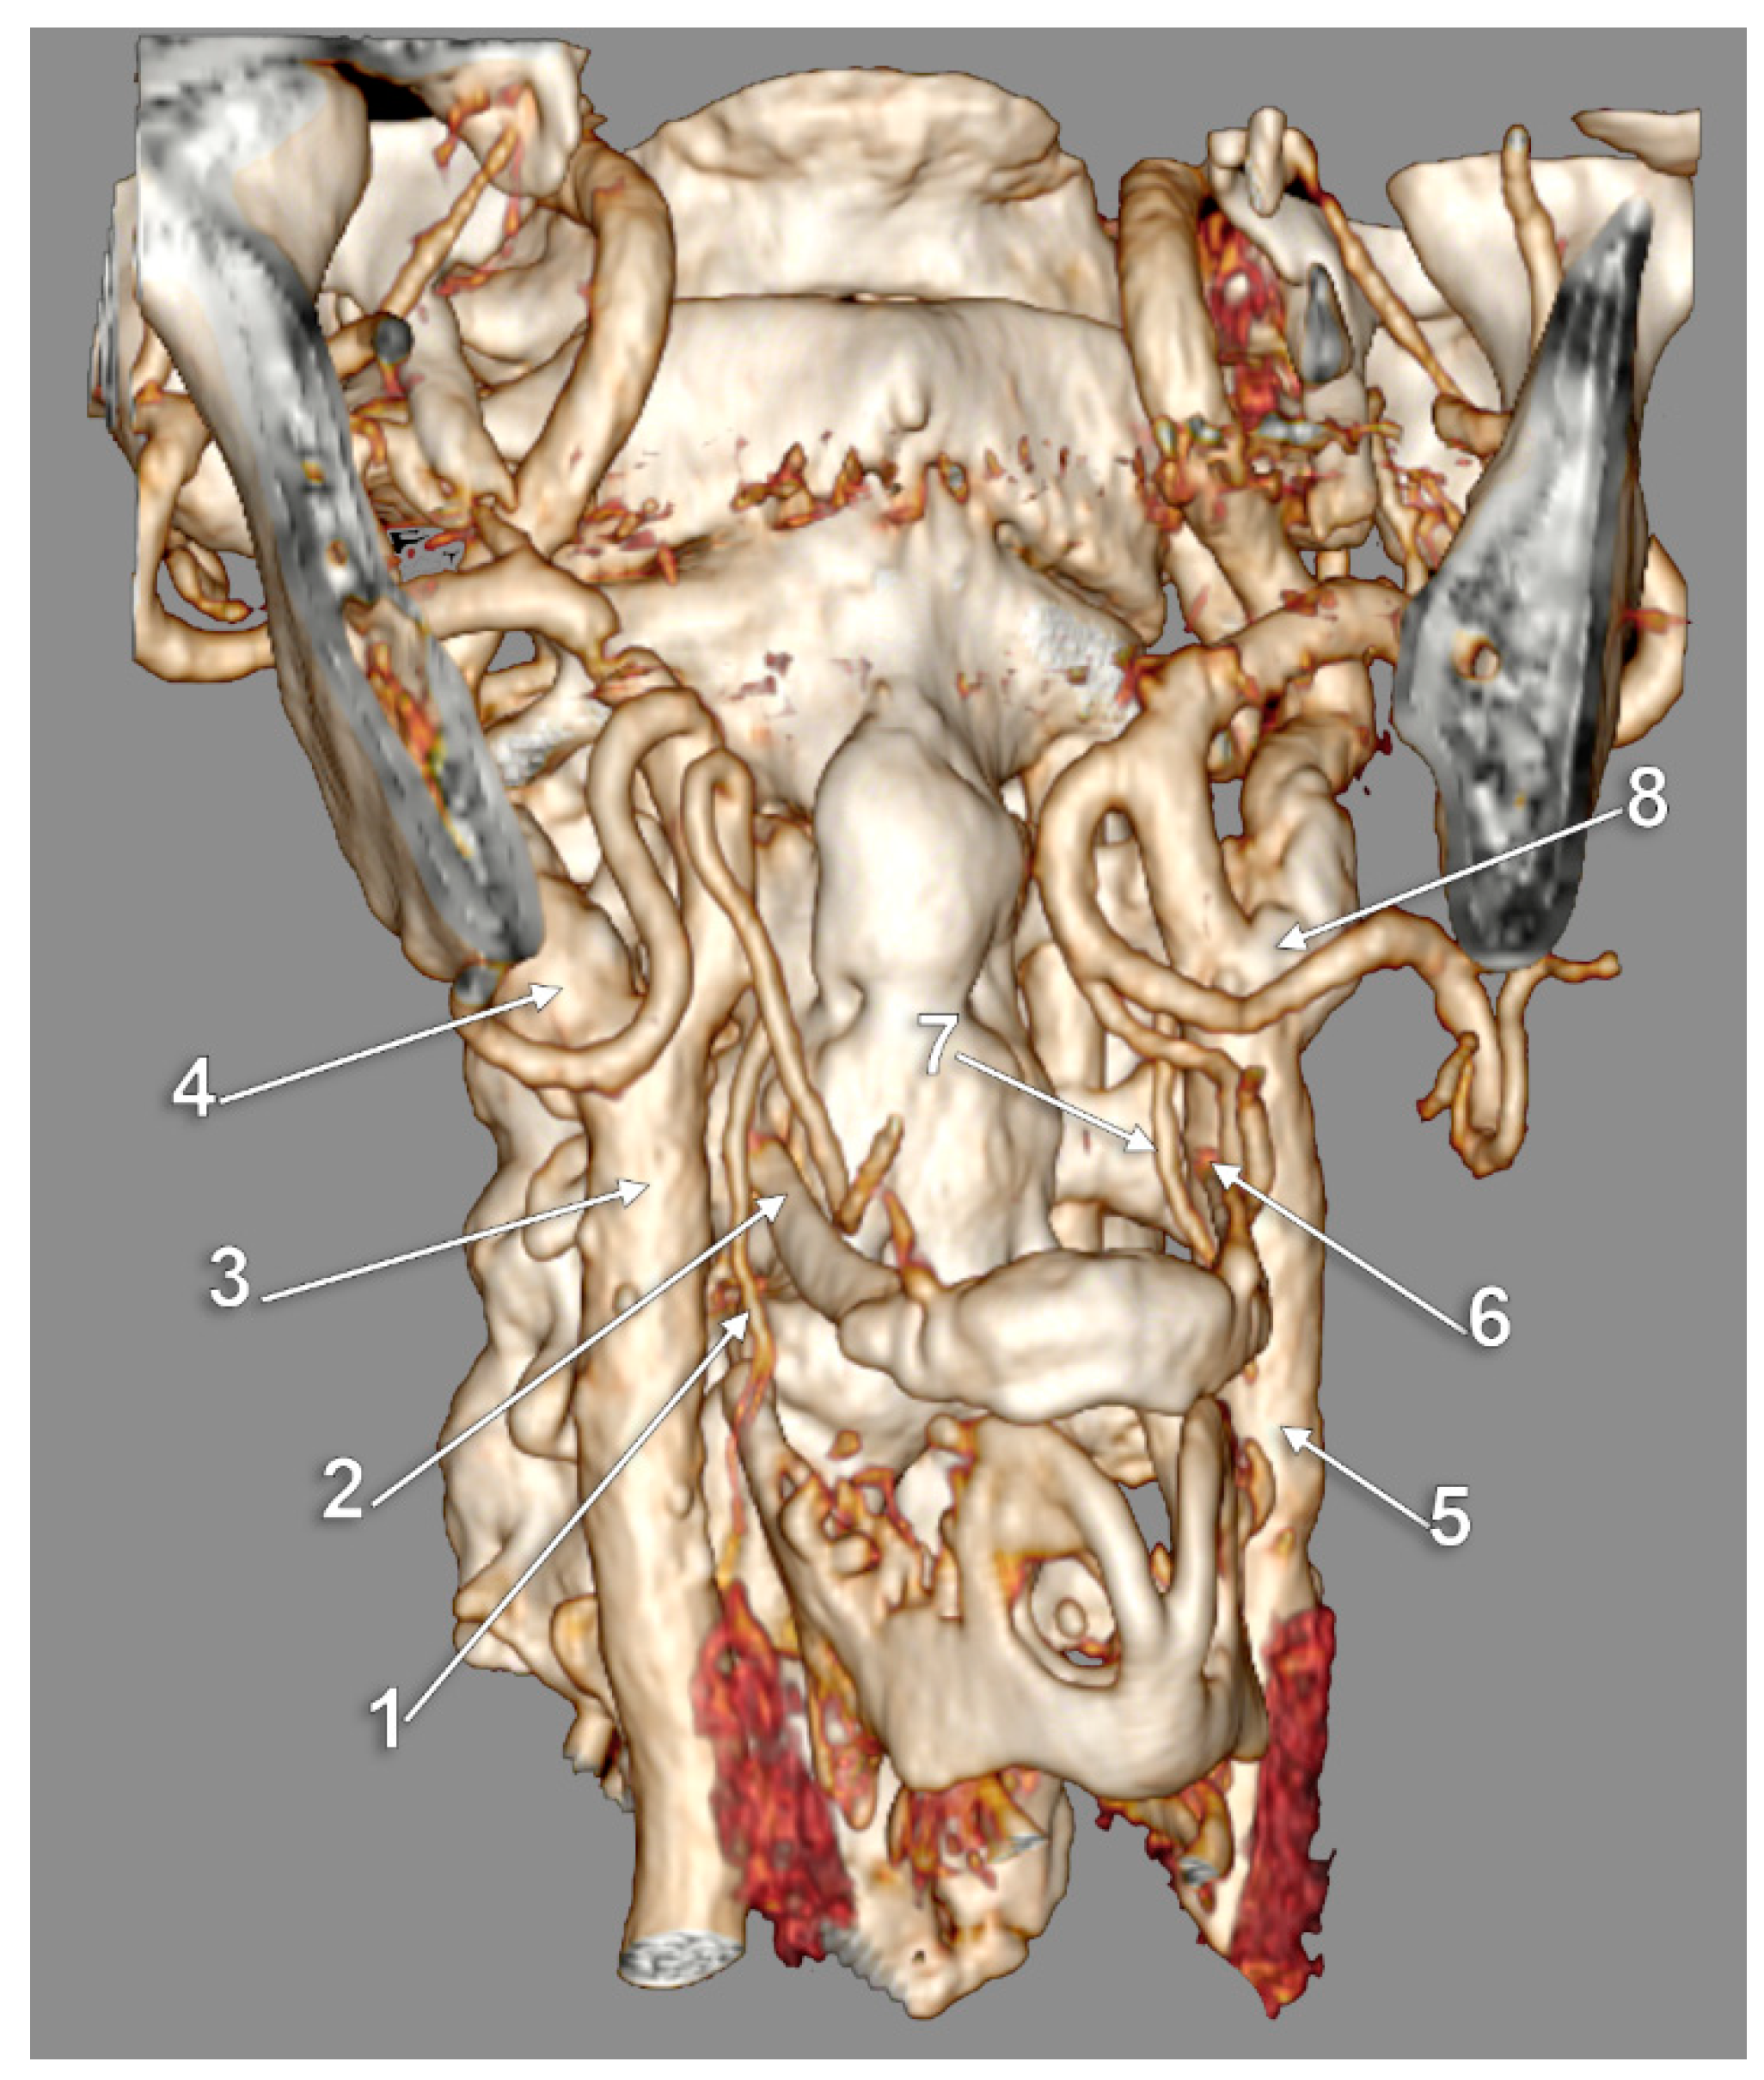

3. Results